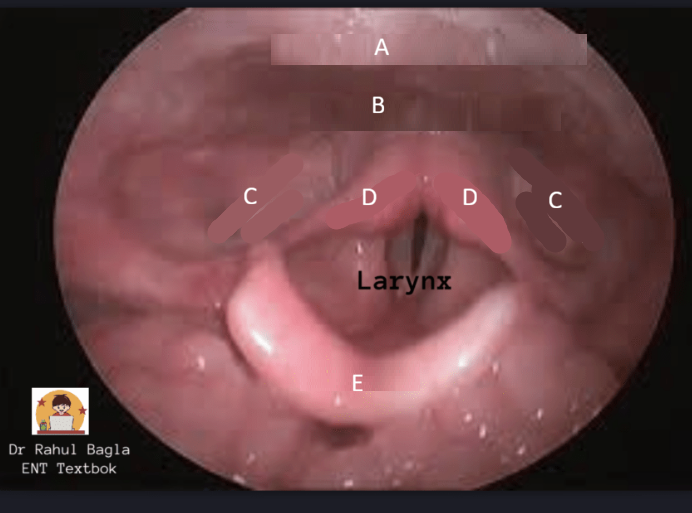

What is this?

Quinsy (peritonsillar abscess)

Treatment: drainage of the abscess, antibiotics